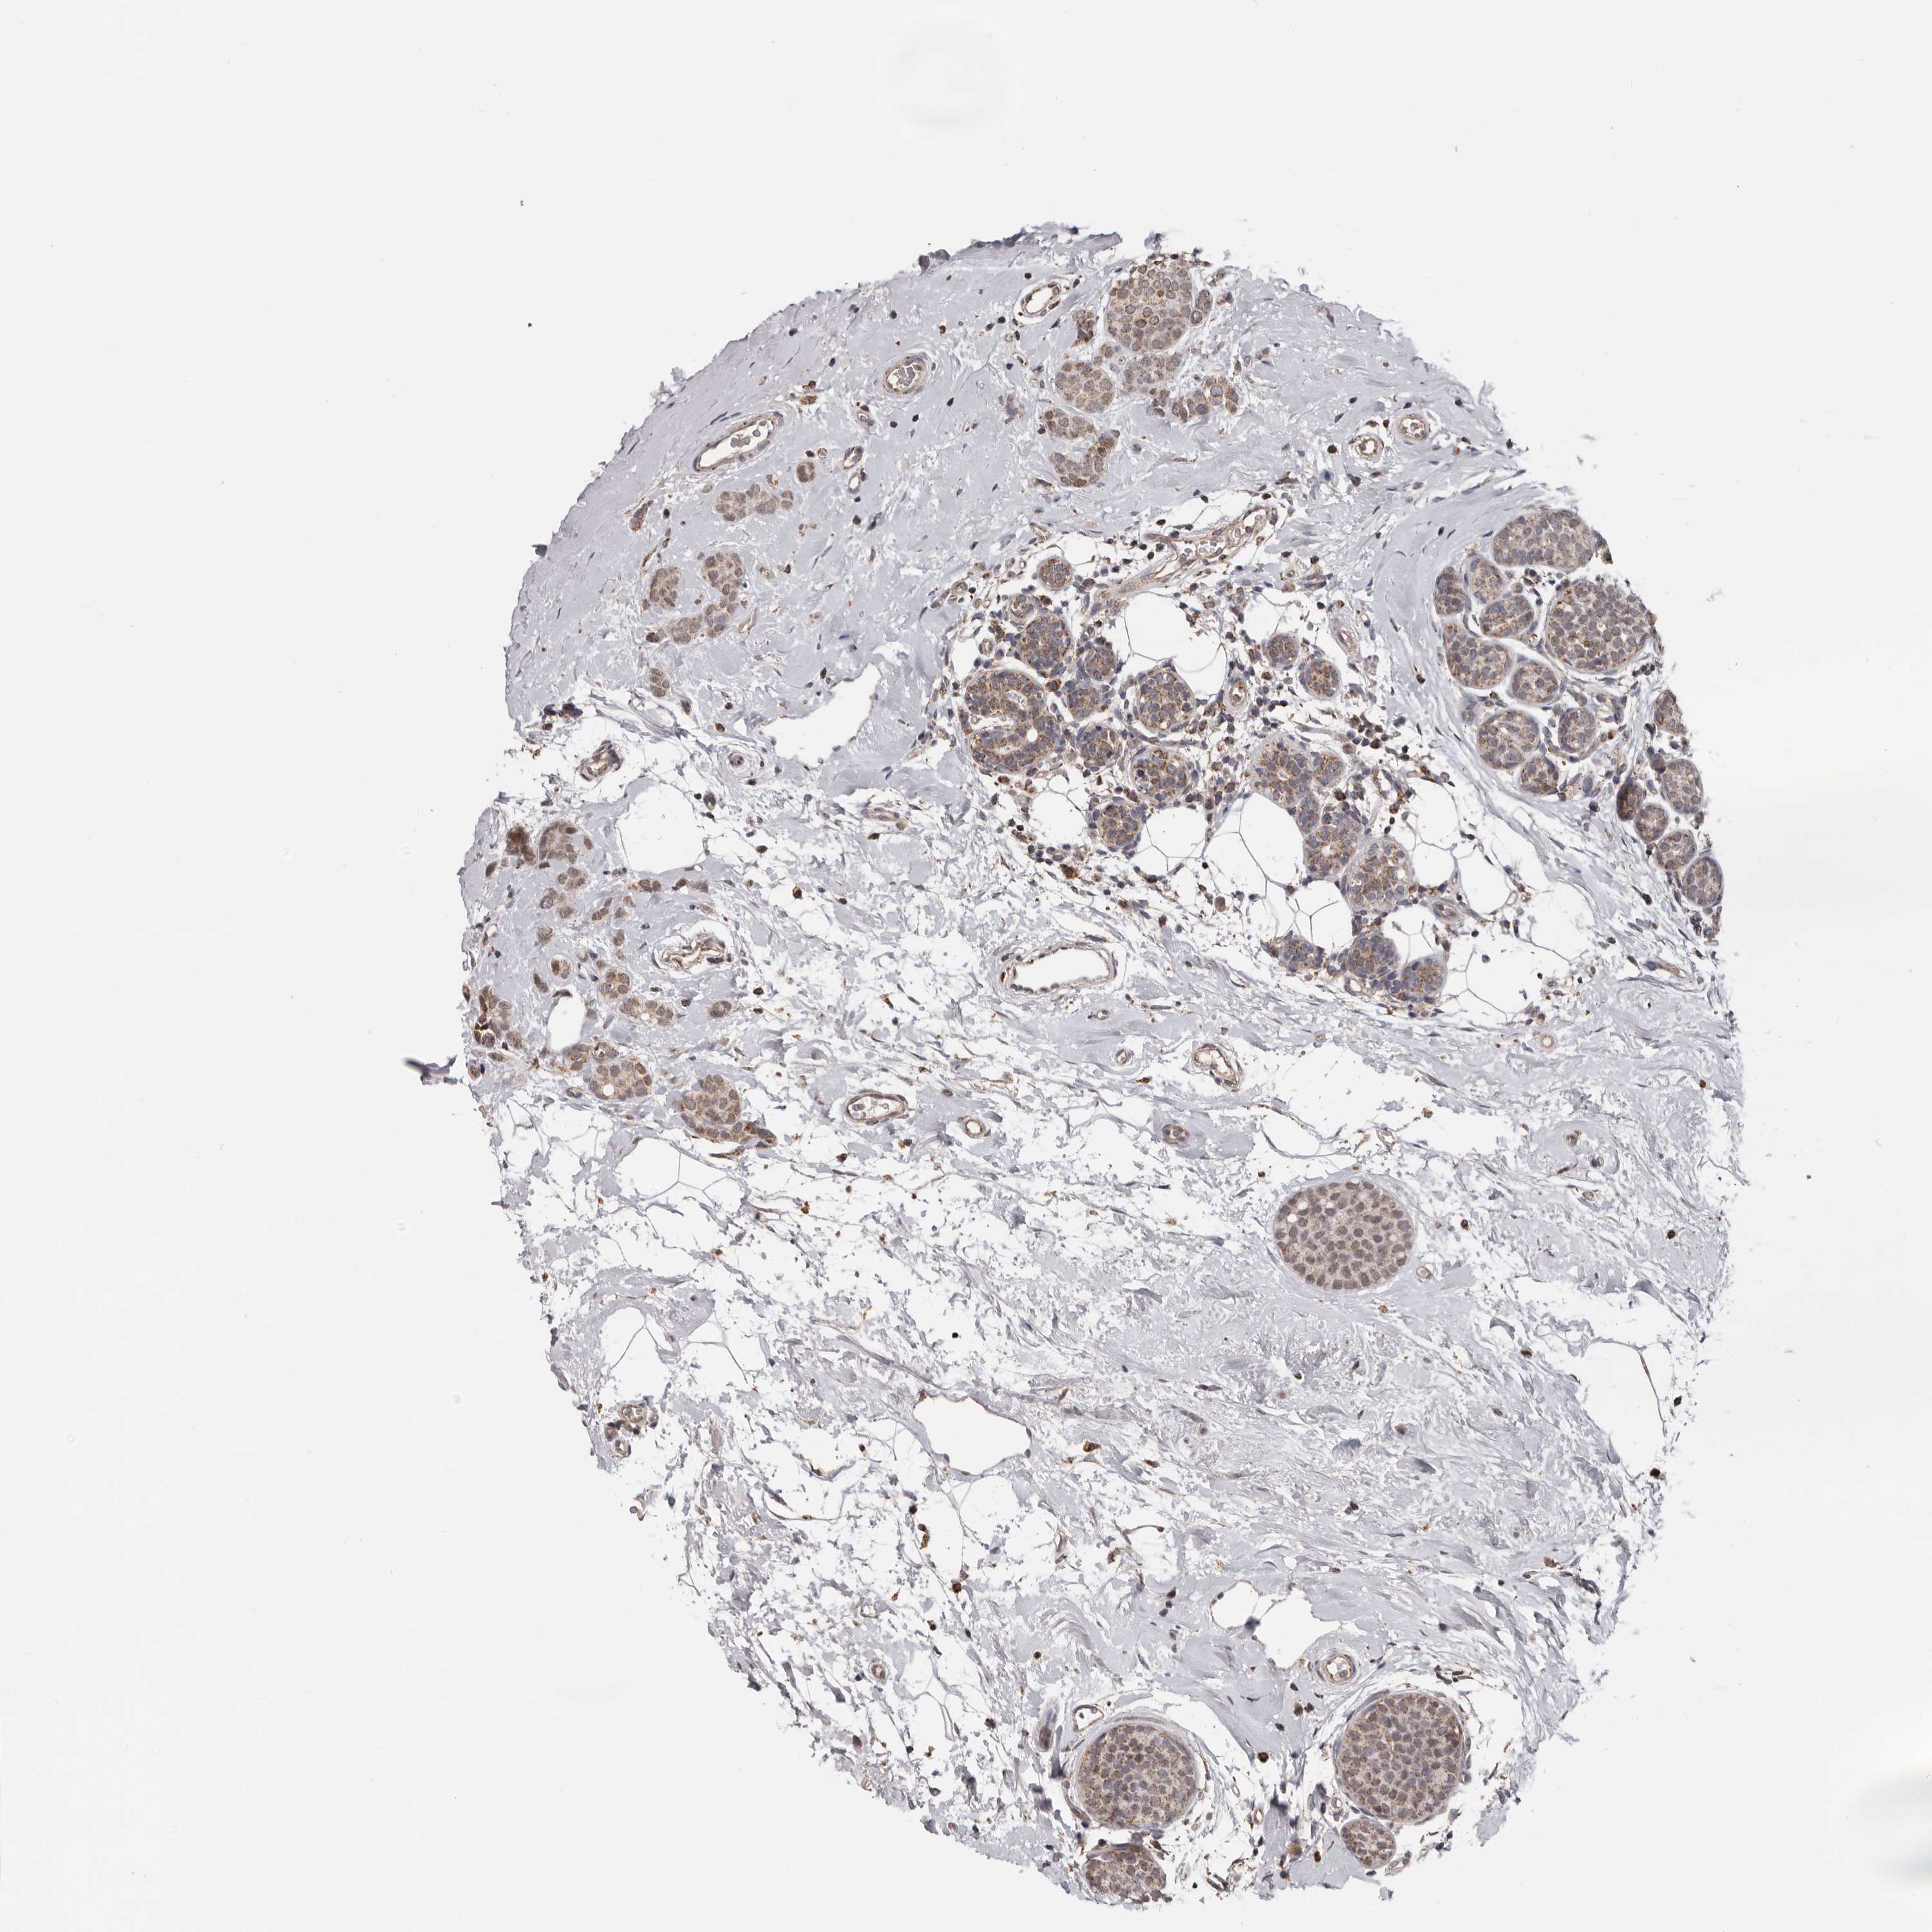

CANCER BREAST CANCER Show tissue menu

BRCA TCGA BRCA VALIDATION PROTEIN EXPRESSION